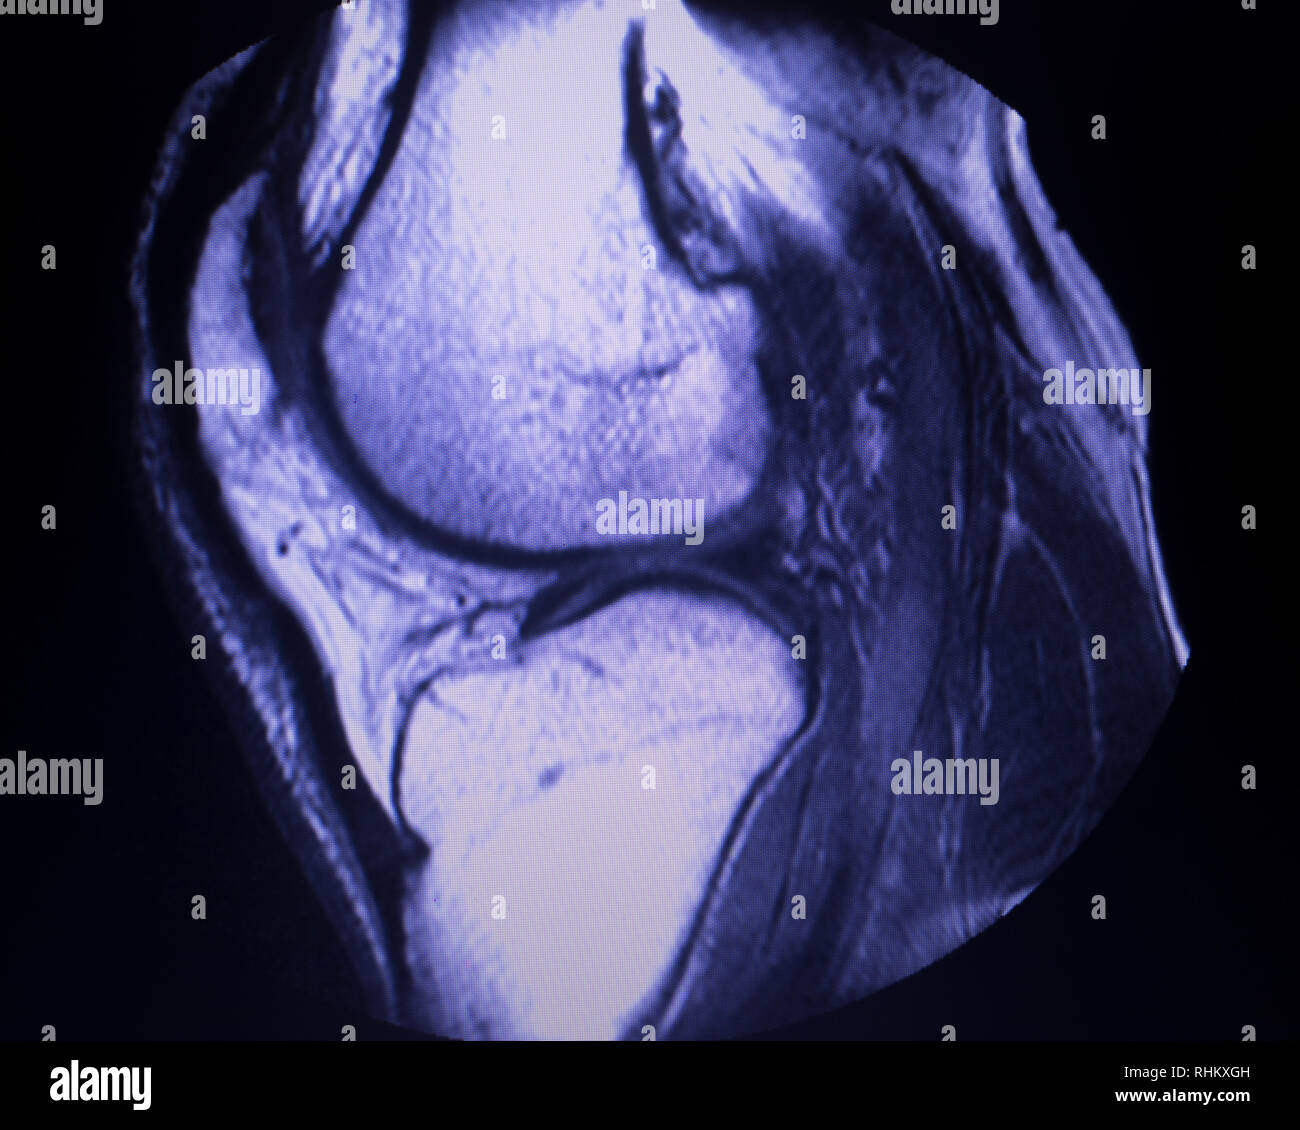

La Resonancia Magnética de rodilla es un análisis imagenológico para estudiar las partes de la rodilla y poder detectar así cualquier lesión que se presente.

Se trata de un examen indoloro, seguro y no invasivo. Resulta muy útil para detectar problemas en la rodilla, en sus partes más comunes como articulación, cartílagos, ligamentos o tendones.